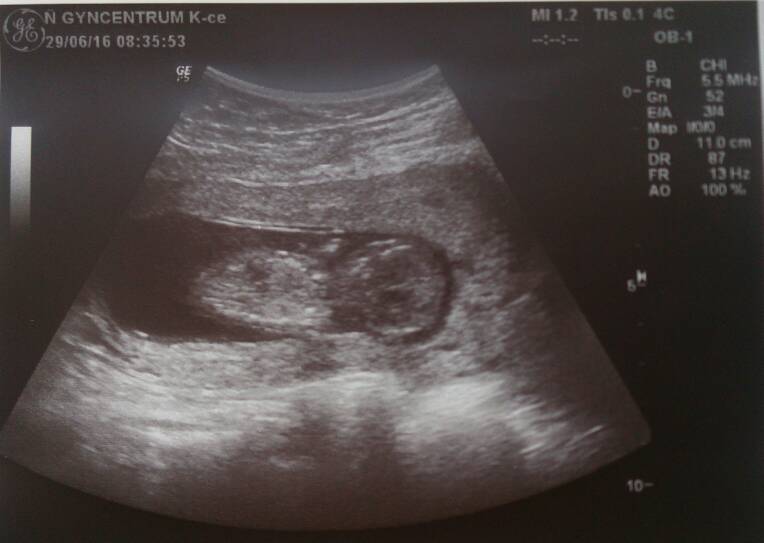

Maluch rośnie i ma się świetnie :-) wg usg 12t4d także idealnie:-D

Serducho pięknie bije

Pomału odstawiamy leki, póki co zmniejszam dawki i duphastonu i luteiny

A to moje szczęście <3

1467203329-1d1mld.jpeg